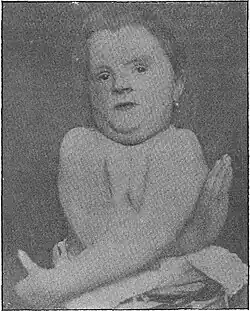

| Adult male patient described by Marie and Sainton, 1898 | |